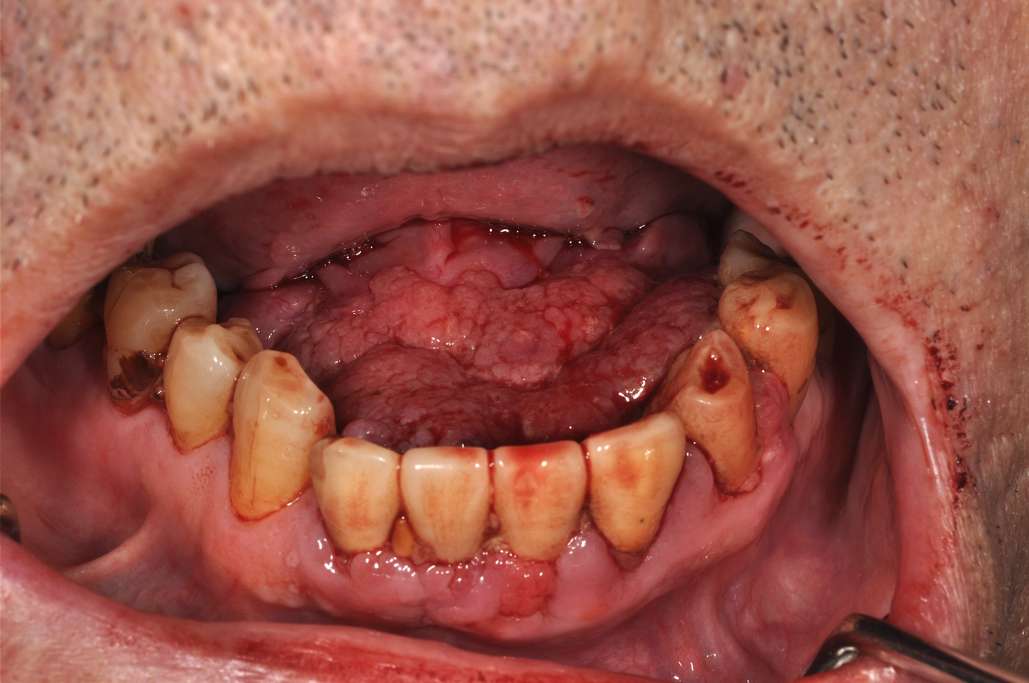

口腔がんの症状がある場合、医師は生検を要求する場合があります。特に、病変が少なくとも 2 週間続いている場合には、生検を指示する場合があります。

口腔がんのその他の症状には次のようなものがあります。

- 唇、口、喉の痛み、刺激、しこり、または厚い斑点

- 口の中の白または赤い斑点

- 口の痛み

- 口内出血

口腔がんがどのようなものであるかについて詳しく学びましょう。

医師は生検を行うことで口腔がんを検査できます。これには、口内の病変から細胞または組織を除去することが含まれます。

口内炎、持続的な痛み、またはその領域の出血などの口腔がんの症状がある場合、生検が必要になる場合があります。生検では、がんの発生を意味する異常な細胞変化が示される場合があります。